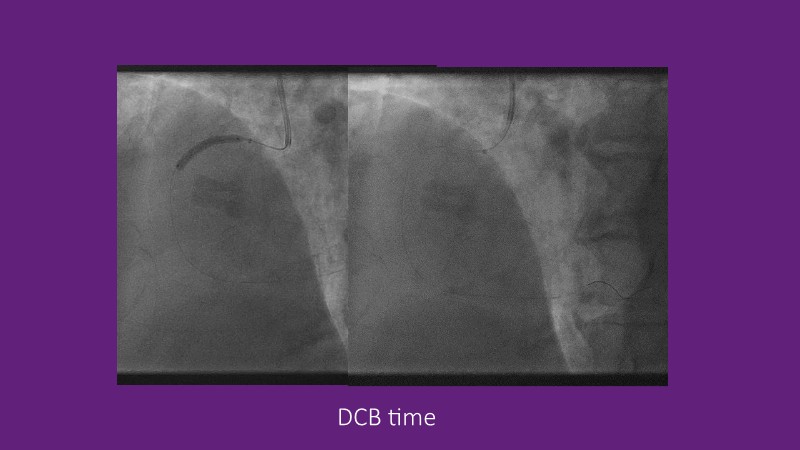

Leave nothing behind - Advancing DCB strategies in complex interventions

Explore cutting-edge strategies for optimizing drug-coated balloon (DCB) procedures in this session. Uncover practical tips to improve outcomes, review key indications, and examine international consensus on DCB use. Case presentations and expert discussions offer insights to refine your approach.